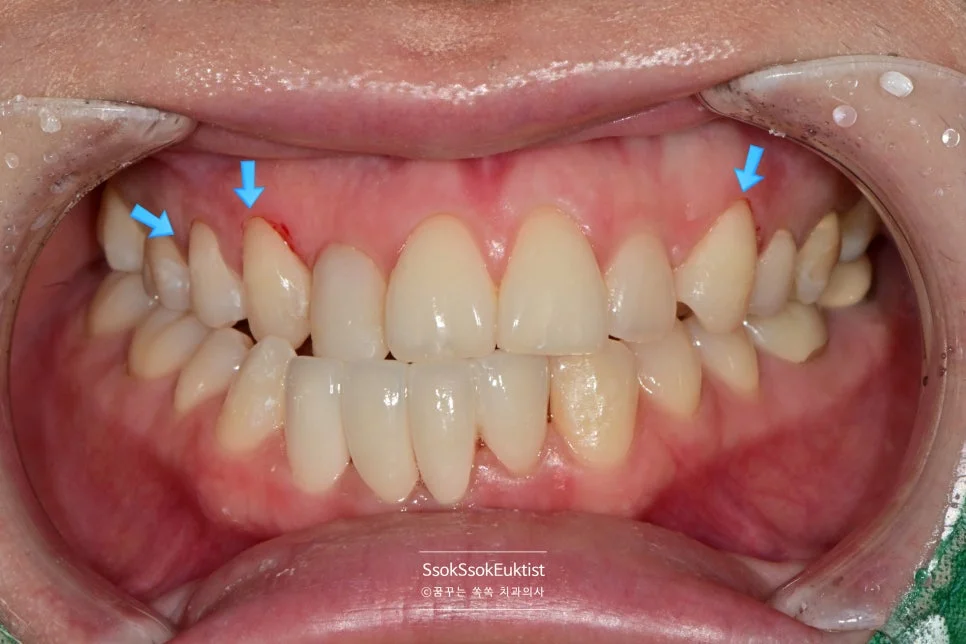

치료 전 정면 교합 사진 — 아래 앞니의 배열 상태 확인

진단 사진 — 가지런하지 않고 정출된 치아, 레진 치료가 되어 있는 부위 (화살표)

아래 앞니의 모양 개선을 원하는 증례입니다.

사진상에서 왼쪽(환자분의 오른쪽) 앞니 두 개가 주변 치아 대비 살짝 솟아 있는 것, 그리고 가지런하지 않은 모양이 내심 오랫동안 마음에 쓰이셨던 것 같습니다.

가지런하지 않은 아래 앞니 (화살표) — 크라운 치료가 필요한 상태